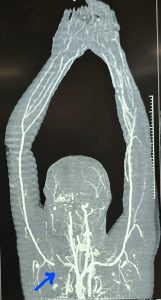

कटे धमनी को dacron ग्राफ्ट लगाकर जोड़ा गया।

कॉलर बोन को काटने के बाद पाया गया कि धमनी लगभग 3 सेमी तक पूरी तरह क्षत-विक्षत हो चुकी थी। इसे जोड़ने के लिए 7×30 मिमी. साइज का डेक्रॉन ग्राफ्ट (कृत्रिम नस) लगाया गया। सर्जरी के दौरान लगभग 5 यूनिट रक्त चढ़ाया गया और करीब 4 घंटे की कड़ी मशक्कत के बाद हाथ में पुनः रक्त प्रवाह शुरू हो सका। इस दौरान ब्रैकियल प्लेक्सस (तंत्रिका तंत्र) को पूरी तरह सुरक्षित रखा गया, क्योंकि इसमें क्षति होने पर हाथ में स्थायी लकवे की संभावना रहती है। ऑपरेशन के बाद कॉलर बोन को प्लेट लगाकर वापस जोड़ दिया गया